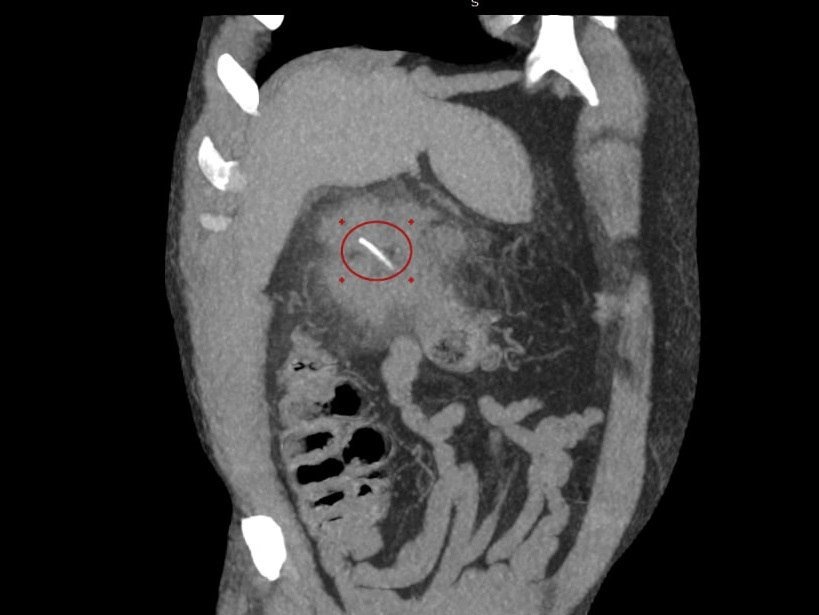

Мужчина обратился в медучреждение с жалобами на боли в правом подреберье. В результате врачи обнаружили у него инородный предмет костной плотности в проекции правого фланга толстой кишки.

Во время обследования было выявлено, что кость длиной примерно в 3 сантиметра проделала отверстие в стенке толстой кишки в районе печени. Именно поэтому пациенту экстренно сделали операцию, которая прошла успешно.